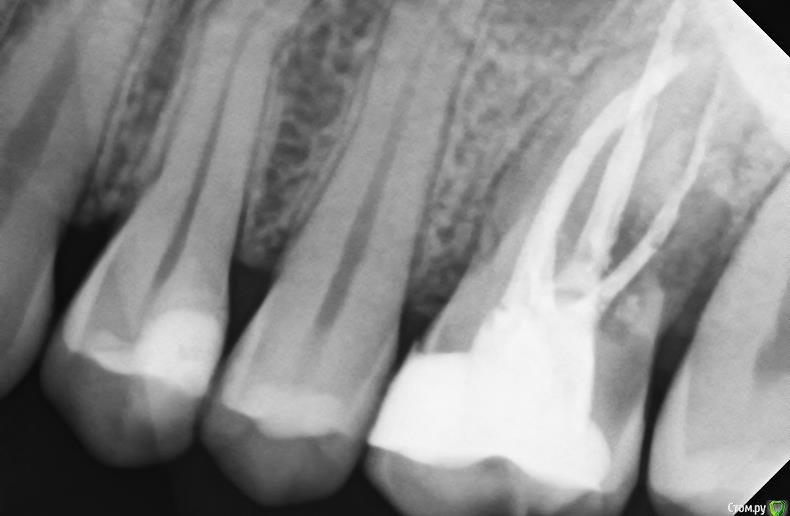

sole13 Опубликовано 18 декабря, 2017 Поделиться Опубликовано 18 декабря, 2017 Уважаемые врачи,посмотрите, пожалуйста, снимок зуба Очень хочется сохранить зуб 7 лет назад 26 зуб -удалили нервы, залечили зуб 2 года назад сильные нарастающие боли и несколько врачей сказали что зуб не подлежит восстановлению, т к воспаление на уровне кости (?), пропила антибиотики, один врач взялся без гарантии перелечивать каналы: 2 перелечил, а при прохождении третьего пошла кровь и он сказал, что корень был препарирован при удалении нервов ранее=> поэтому ситуация с воспалением, месяца 3-4 я проходила с пастой на основе кальция(?) зуб не болел, потом запломбировали на протяжении этих 2 лет при простывании 2 раза в год болит зуб, иногда пью антибиотики иногда сам прорывает гной через десну и боль проходит. 1. реально ли сохранить такой зуб? как?2. темное на снимке - это разреженная кость ( идет на убыль из-за воспаления)? можно ли как-то удалить воспаленные ткани и восстановить кость за счет искусственного материала?3. не могу понять по фотографиям 2015 и 2017 годов: есть ли положительная динамика? спасибо!2017 год 2015 год Ссылка на комментарий